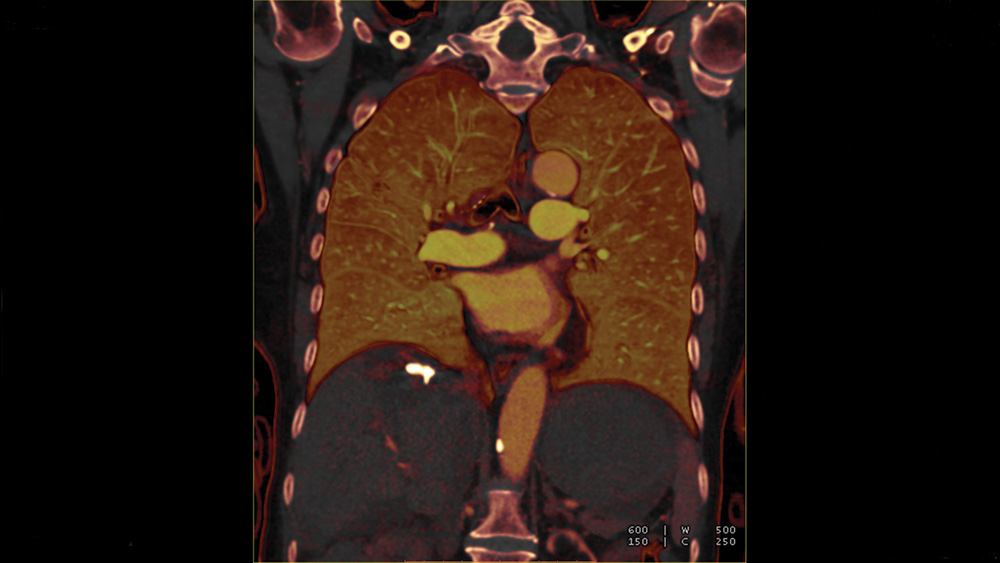

One of the most important recent advances in thoracic radiology and in vascular imaging in general has been the implementation of dual-energy CT.

Dual-energy CT allows the differentiation of materials with large atomic numbers such as iodine. Dual energy CT angiography can evaluate perfusion defects in cases of pulmonary embolism.

Although not as sensitive and specific as scintigraphy, it is highly accurate when there is complete occlusion of pulmonary arteries. The iodine perfusion map may also be used for the follow-up of pulmonary embolism. Dual energy CT may also be helpful in the evaluation of pulmonary nodules.

Using dual-energy CT, solitary pulmonary nodules can be characterized and malignant pulmonary nodules may be distinguished from benign lesions by providing information on the degree of enhancement and the presence of calcification.